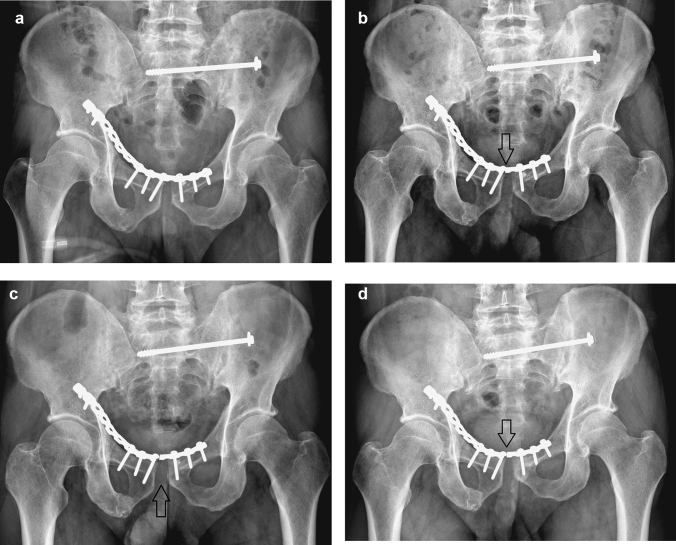

Nine patients (32%) experienced implant failure, including four with screw loosening and five with plate breakage during the follow-up. Among the implant failure patients, one patient experienced it immediately during hospitalization, seven had implant failures at 3 months post-operatively, and the remaining patient had implant failure at 6 months postoperatively. Two patients met the criteria of loss of reduction. Only one patient who experienced implant failure immediately during hospitalization underwent a secondary operation for a revision of the fixation (Fig. 1). Another eight patients with implant failures underwent conservative treatment because they were asymptomatic (Fig. 2).

Fig. 2.

Radiographs of the pelvis in an anteroposterior view after anterior plating and posterior screw fixation. a Immediately postoperative. b At 3 months, symphysis plate breakage was observed (seen at arrow). c At 6 months, the pubic symphysis distance mildly widened (arrow). d At 12 months, the pubic symphysis distance became stable without an interval change

In all patients, the average of PSD decreased obviously, from 37 mm to 5.3 mm immediately after surgery. However, compared with postoperative immediate PSD, PSD increased continuously until 6 months after surgery (Table 1).